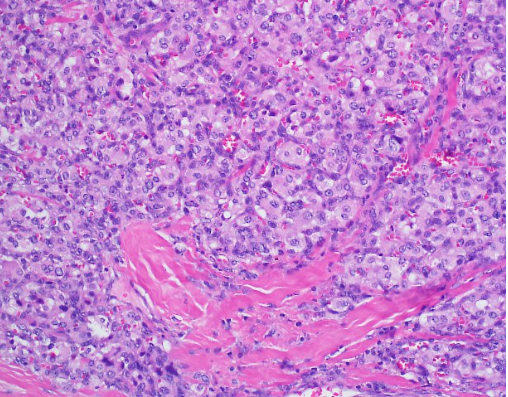

Case Presentation: We report the case of a 43-year-old man who presents to our institution with recurrent episodes of dizziness, headaches and syncope. He had a history of uncontrolled hypertension that was diagnosed as a teenager. His admitting blood pressure was 174/103 mmHg and he had a heart rate of 108. On physical exam, he was obese and appeared uncomfortable. He had some mild, bilateral neck swelling. Biochemical evaluation resulted in urine and plasma metanephrines. A CT scan of the neck’s soft tissue revealed a 0.8 cm right carotid body tumor, a 1.7 cm left carotid body tumor, and a 1.2 cm right glomus vagale tumor, suspicious for paragangliomas (PGLs). Given the magnitude of this patient’s symptoms and lab findings, surgery was performed. Initially, the right carotid body tumor was embolized by Neurosurgery and then Otolaryngology did a right neck dissection to remove the right carotid body and glomus vagale tumors. While the patient did have improvement in his symptoms, he unfortunately developed right facial nerve paresis, a common surgical complication. Histopathologic analysis returned consistent with PGLs and negative for malignancy. Interestingly, the patient’s brother also had a similar presentation in his 40’s consisting of headaches and dizziness. He was diagnosed with isolated bilateral carotid PGLs and subsequently underwent surgery and radiation. Unfortunately, his brother was at another institution and due to insurance issues, was unable to receive genetic testing. Considering the family history of PGLs, mutations for our patient were sent for succinate dehydrogenase (AF2, A, B, C and D) as well as Neurofibromatosis-1 (NF-1). He tested heterozygous for the presence of a Succinate Dehydrogenase complex subunit D (SDHD) c.13_14delTG pathogenic mutation, consistent with the diagnosis of Hereditary Paraganglioma-Pheochromocytoma Syndrome type 1. This pathogenic mutation consists of a frameshift resulting in a truncated protein.